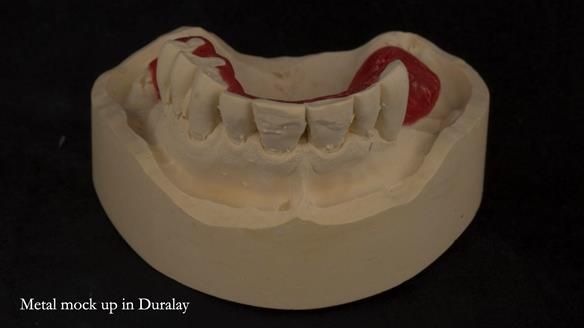

A metal-based upper RPD was made,

with metal backings incorporated to future-proof the design

should further teeth fail.